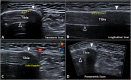

Ultrasound imaging is widely used to evaluate the neuromusculoskeletal system, and recently, a particular interest is mounting in assessing the bone tissue and fractures. Ultrasound can be considered a valuable diagnostic tool to perform a first-line evaluation of bone tissue, especially in particular settings without direct access to X-ray imaging and/or in emergency conditions. Moreover, different healing phases of bone fractures can be accurately assessed by combining the B-mode modality and (high-sensitive) color/power Doppler optimizing the management of patients-e.g., planning of progressive loads and rehabilitation procedures. In this review, we summarized the role of ultrasound imaging in the management of bone fractures and described the most common sonographic signs encountered in the daily practice by assessing different types of bone fractures and the progressive phases of the healing process.